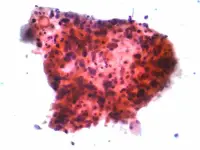

Il cancro

Cancro è una parola ancora temibile. Nell'immaginario collettivo ha quasi sempre una prognosi infausta quando invece i dati statistici ci raccontano sempre più spesso come stiano aumentando le guarigioni e le speranza di vita dopo la diagnosi.

Il cancro è sempre più curabile grazie alle diagnosi precoci e alle scoperte mediche in tutti i campi.

La presentazione che segue prende in considerazione tutti questi aspetti e tratta poi in particolare del cancro alla mammella (il più diffuso nel sesso femminile), del cancro al polmone che fino a questo momento ha colpito di più i maschi e del linfoma che interessa bambini, adolescenti e terza età.